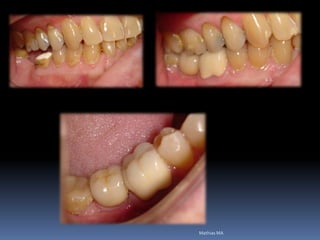

Bruxismo e mordida cruzada profunda

•Necessidades de reabilitações prévias

Dentística, periodontia, cirurgia, prótese, endodontia , ortodontia e DTMs

•Áreas de interesse implantar

Perdas dentárias , tecido ósseo e tecido mucoso